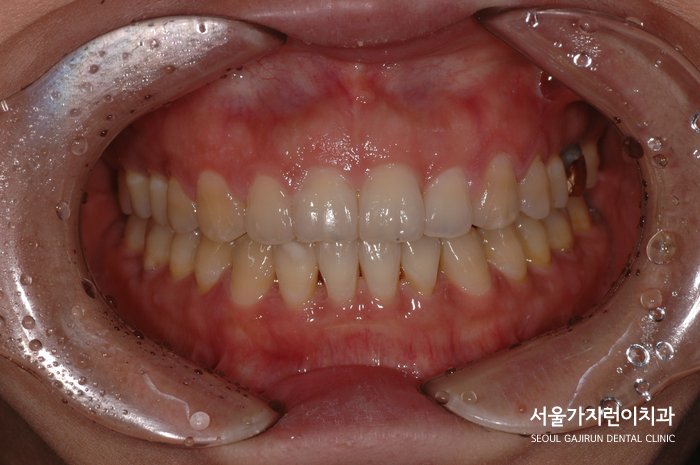

환자분의 경우 하악에 미니스크류를 식립해 뒤로 당겨주었고 벌어진 상악의 앞니는 치열을 이동시켜 빈 공간을 닫았는데요. 보기에는 가벼운 벌어진 앞니였지만 사실 클래스 3 부정교합에 해당하는 케이스였기때문에 전체적인 교정이 필요했습니다.

현재 환자 분의 경우 치료 후 5년이나 지났는데도 좋은 치열을 유지하고 계신데요. 별다른 이슈 없이 저희 치과를 내원해 관리를 받아보고 계십니다. 이렇듯 간단해보이는 앞니 교정도 전체교정이 필요한 상태가 있을 수 있는데요. 앞니의 벌어짐은 그 원인에 맞게 진료하는 게 무척 중요하니 이 케이스도 있다는 점 확인해보고 문제가 있을 때 교정전문치과 본원을 찾아주면 좋겠습니다.